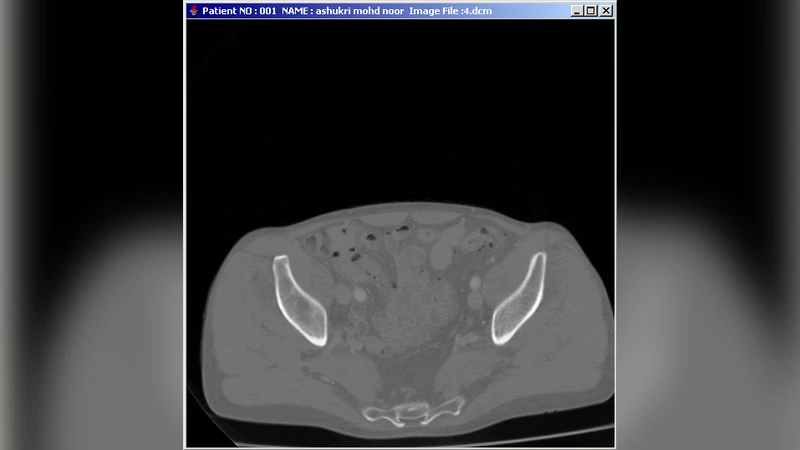

본 논문은 병원 내 방사선과와 중환자실·응급실 등 연계 부서 간의 영상·데이터 공유 문제를 해결하기 위해 Java 기반의 분산 객체 의료 영상 모델(DOMIM)을 제안한다. CORBA와 JDBC를 결합한 아키텍처로 이기종·레거시 시스템을 통합하고, 실시간 이미지·음성·영상·주석 교환을 지원한다. 이를 통해 원격지의 방사선과 의사와 임상의가 협업할 수 있는 환경을 제공한다.

DOMIM은 의료 현장의 복합적인 요구를 충족시키기 위해 객체 지향 분산 컴퓨팅과 데이터베이스 연동 기술을 융합한 설계가 돋보인다. 핵심은 CORBA 기반의 IDL(Interface Definition Language)로 정의된 인터페이스와 ORB(Object Request Broker)를 통해 이기종 시스템 간의 투명한 호출을 가능하게 한 점이다. 특히 의료 영상은 DICOM 표준을 따르는 대용량 바이너리 데이터이며, 이를 실시간으로 전송하기 위해 IIOP(Internet Inter‑ORB Protocol)와 이벤트 서비스(Event Service)를 활용해 비동기식 스트리밍을 구현한다.